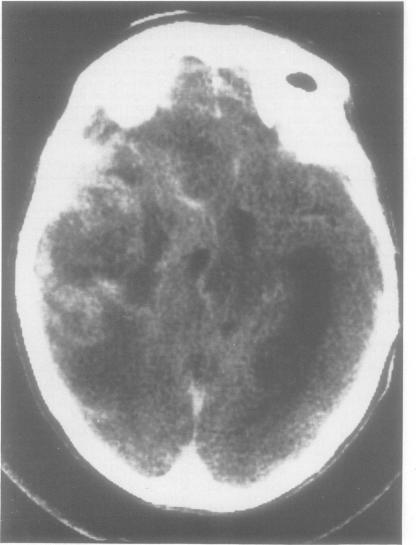

Asymmetry of pathology in Alzheimer's disease.

J Neurol Neurosurg Psychiatry. 1987 Oct;50(10):1384-6. doi: 10.1136/jnnp.50.10.1384.